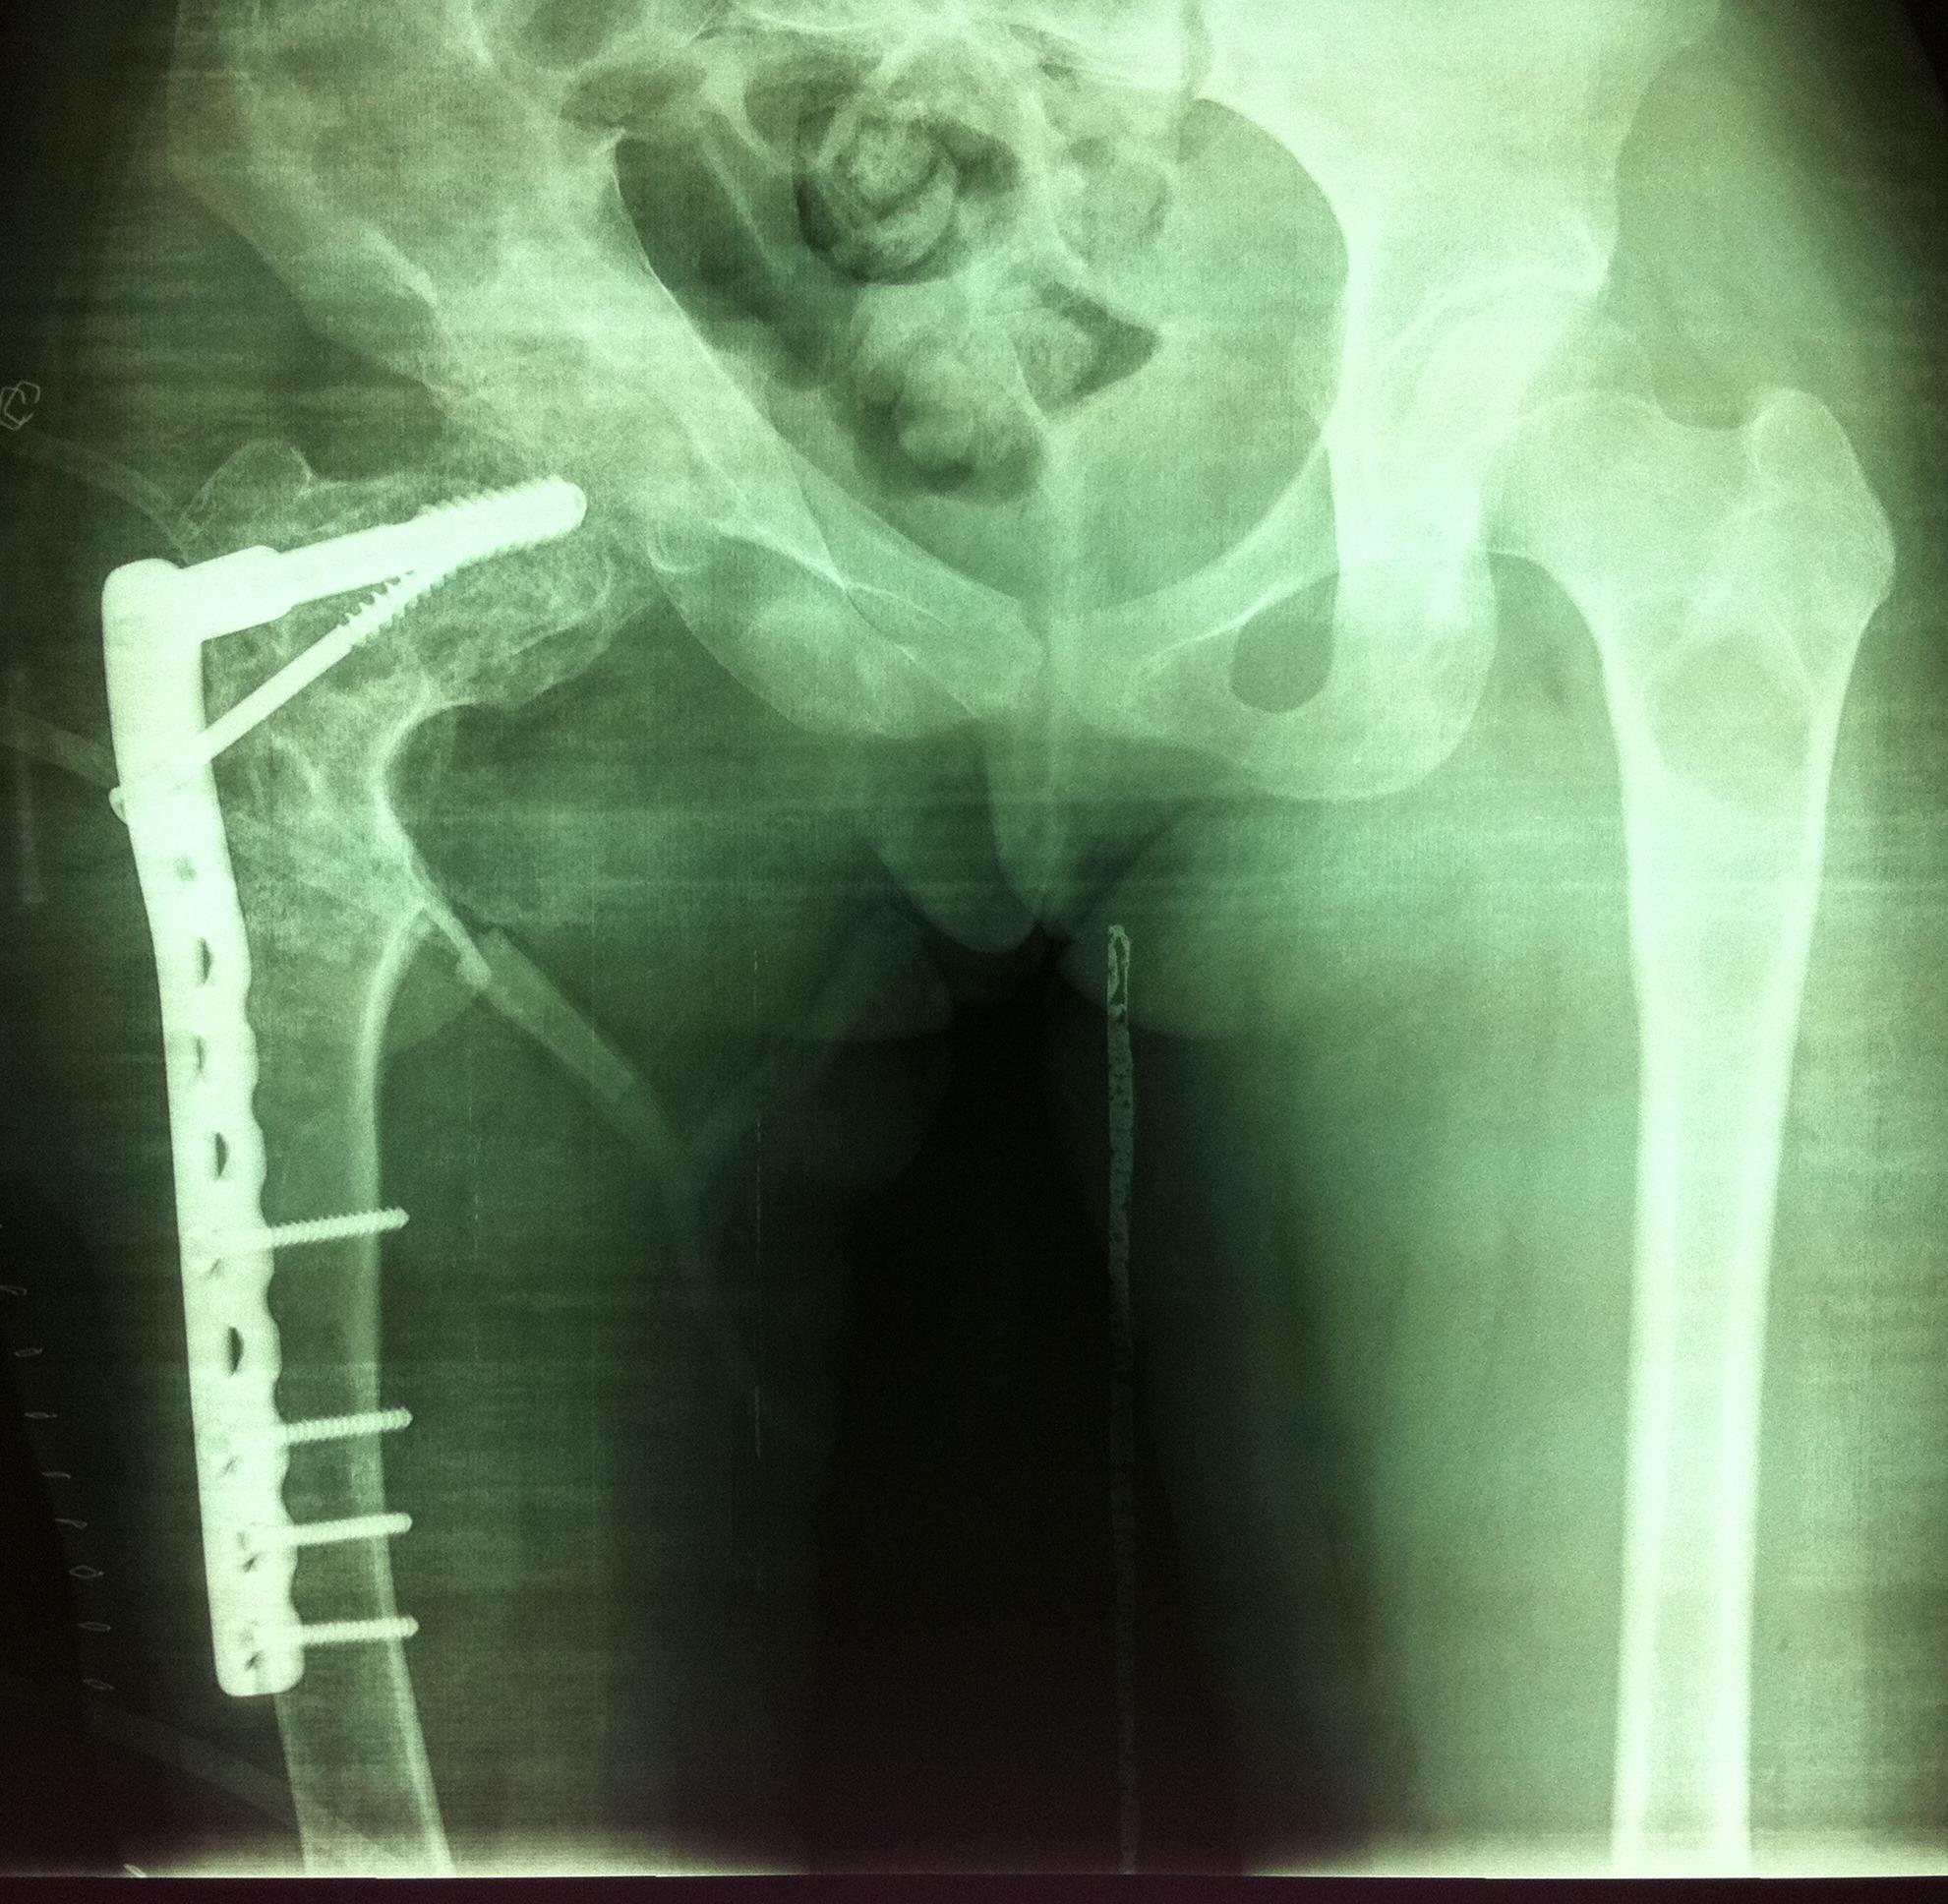

对于严重髋内翻畸形颈干角<60°,且股骨头下方有骨赘形成(如图1),肢体短缩严重者:如果继续使用DHS钢板,力求使颈干角恢复到120°时,此时髋关节头臼咬合已不匹配,臀中肌张力会更大,甚至肢体延长过多会引起坐骨神经症状。对这类患者我们采用DCS钢板,缩减颈干角为95-105°,术后患者髋关节头臼咬合基本匹配,臀中肌经轻度松解也可适应,同时也减少了坐骨神经损伤的风险。26例中我们使用DCS钢板6例,术后均达到满意的效果。

图1女性,18岁,术前肢体短缩9cm图2 术后力线纠正

图3 术后肢体等长

图4 女性,17岁,术前肢体短缩4cm图5 术后2年复查肢体等长,截骨处愈合